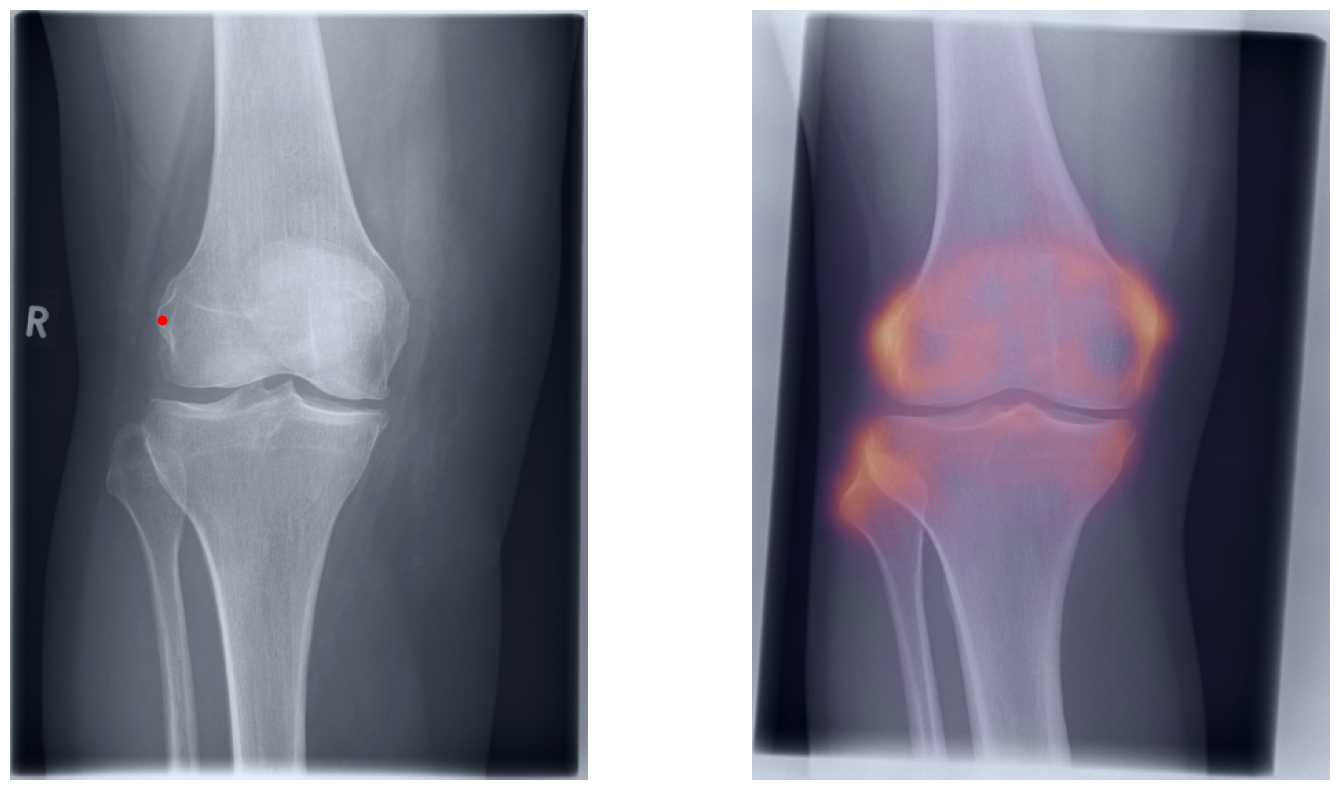

Artificial intelligence (AI) has shown great potential in assisting radiologists with musculoskeletal (MSK) assessments across various anatomical regions1,2,3,4. However, most existing tools are narrowly tailored for specific anatomies or rely on segmentation-based methods as a basis. To address these limitations, we propose a versatile and generalist AI-based approach for landmarks matching. In contrast to typical generalist landmark matching approaches that depend on automatically identified, optimally descriptive landmarks5,6,7, our use-case has to be based on manually selected landmarks tailored for MSK measurements. As these landmarks are potentially subotimal for precise matching, we employ an AI-based method8 that first performs multi-scale dense image matching between the reference and target images independently of the landmarks. The AI uses a combination of transformer and convolutional neural networks to establish a multi-resolution descriptive feature representation of each position within the images, allowing to define correspondences between the reference and target images. In a subsequent step, landmark positions are transferred to the target image based on these correspondences, with the determination of final locations benefiting from the redundancy of the dense matching. This enables robust automation of landmark matching from a reference patient across an entire cohort of target patients. The approach is anatomy-agnostic, enabling the use of the same backbone model for a wide range of anatomical regions and MSK measurements. For more detailed information we refer to our paper.

Once a correspondence between the reference and target radiographs is established, landmark matching can be performed in real-time. This process enables the alignment of individual points and allows for the definition of a predefined set of landmarks that can be mapped onto the target patient. These predefined landmarks can be customized for the automated calculation of specific measurements, which, once defined on a reference patient, can be consistently and automatically transferred to any radiograph within the target cohort.

The process of establishing a dense match between two images relies on abstract feature representations for each position in both the reference and target images. To better understand which information is encoded by the AI, we examined the feature similarities between a specific position within the reference image and the entire target image. Our findings show that the AI captures both semantic and texture features. The matching process utilizes this encoded information, along with precise positional data, to create a reliable mapping between the images.

From Novice to Expert: Annotation Through Imitation